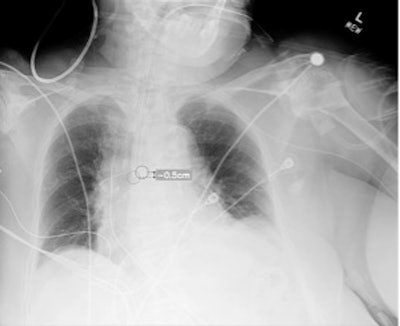

Plain chest radiograph showing overlay from Critical Care Suite, with segmentation of ETT, identification of tube tip and carina, and calculation of distance between them.Plain chest radiograph showing overlay from Critical Care Suite, with segmentation of ETT, identification of tube tip and carina, and calculation of distance between them.Critical Care